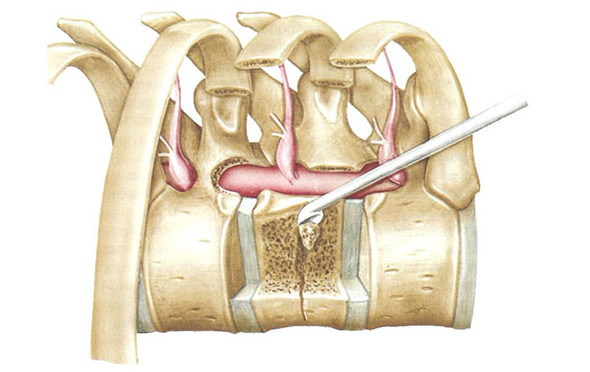

Удаление опухоли при открытом доступе и резекция участка позвонка применялась еще с 30-х годов прошлого столетия, однако эта операция весьма опасна серьезными осложнениями: кровотечение из сосудов образования, нарушение питания спинного мозга, перелом позвонка. Ввиду риска таких последствий вмешательство применяется изредка и при серьезных показаниях, таких как компрессия спинного мозга или его корешков. Извлечь опухоль полностью при открытой операции технически невозможно, хирург может удалить лишь ее часть, расположенную эпидурально.

Если выхода нет и необходимо такое вмешательство, то предпочтение отдается декомпрессионным методикам, направленным на устранение сдавления опухолью структур спинного мозга. Хирургическое лечение нередко проводится детям, когда введение цементирующего вещества может вызвать остановку роста позвонка и деформацию позвоночника в дальнейшем.